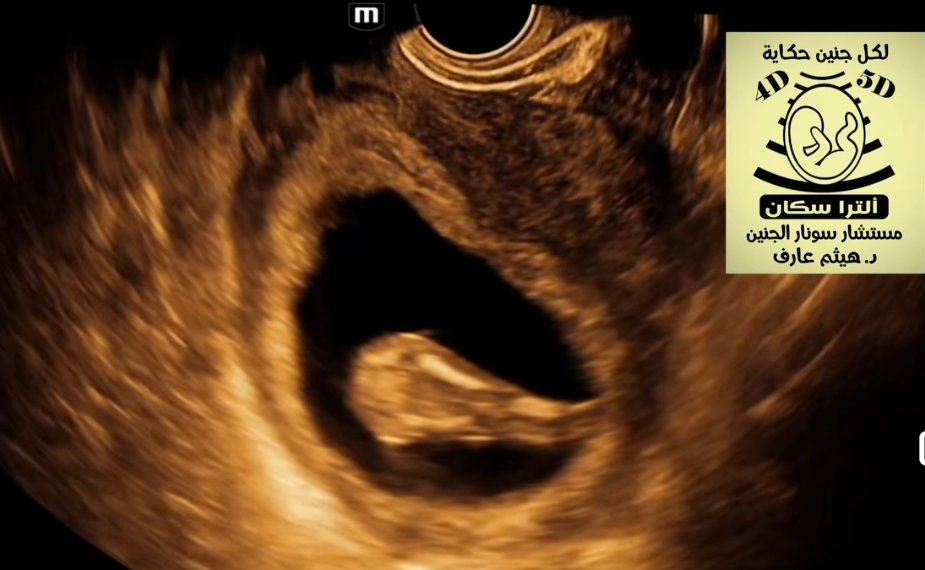

Sirenomelia fetal ultrasound

Lower Limb Fusion: The most characteristic feature, where legs are conjoined into a single midline structure.Single Umbilical Artery: Frequently observed and often originating directly from the abdominal aorta (the “vascular steal” phenomenon).Bilateral Renal Agenesis: The absence of both kidneys is a common association.Severe Oligohydramnios: A lack of amniotic fluid (often due to renal agenesis) is typical in the second and third trimesters, which can make imaging the limbs much more difficult.Additional Anomalies: Non-visualization of the bladder, sacral agenesis (absence of the tailbone), and imperforate anus